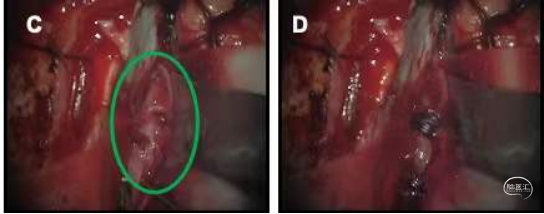

图4. 术中镜下所示 4a右额叶皮层造瘘暴露右侧大脑中动脉动脉瘤(绿圈),左侧为额叶,右侧为颞叶;4b夹闭梭形动脉瘤近端动脉后电凝载瘤动脉;4c沿纵裂向下分离暴露右侧大脑前动脉动脉瘤(绿圈),上为额侧,下为枕侧;4d夹闭梭形动脉瘤载瘤动脉。